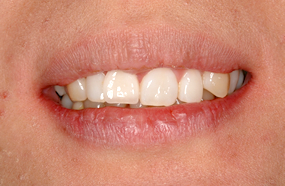

| 部分入れ歯 | インプラント |

|---|---|

![]() | ![]() |

| 入れ歯を固定する金具などに異物感を感じたり、支えている歯に負担がかかることがあります。 | 入れ歯を固定する金具がないので異物感がなく、また他の歯に負担をかけません。 |